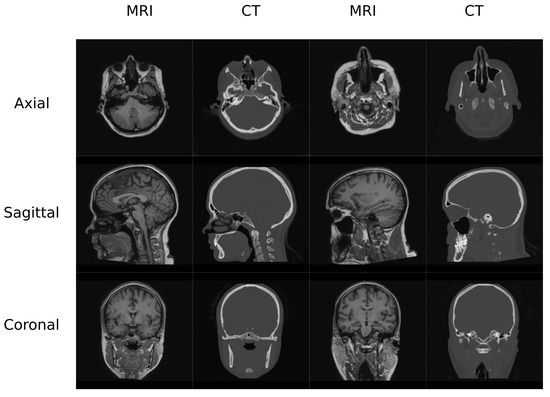

In this work, two datasets were used to train and test the different architectures that are reviewed. The first one (Figure 1) contained MR and CT head pairs from 19 healthy women (34.96 ± 5.23 y/o). MR images were acquired on a GE Signa HDxt 3.0-T MR scanner, and imaging was performed using a 3D T1-weighted sequence with a repetition time of 10.024 ms, echo time of 4.56 ms, inversion time of 600 ms, 1 excitation acquisition matrix of 288 × 288 , isotropic 1 mm resolution, and a flip angle of 12°. Low-dose CT images were acquired on a Siemens Somatom Sensation 16 CT scanner with a matrix of 512 × 512 , resolution of 0.48 × 0.48 mm, slice thickness of 0.75 mm, pitch of 0.7 mm, acquisition angle of 0°, voltage of 120 kV, and radiation intensity of 200 mA.

2.2. Preprocessing

The head database was preprocessed using 3D Slicer built-in modules [32,33]. The preprocessing pipeline included bias correction using the N4 algorithm, rigid registration to align the MR-CT patient pairs as well as to align all the patients in the same orientation, and histogram matching of the grayscale values. Finally, volumes were cropped to 256 × 256 slices in the axial direction since it is easier to have a dimension which is a power of 2 in deep learning applications. This occurs due to the network operations, which half and double the spatial dimensions of the input. Figure 1 depicts examples of the volumes in this database.

Figure 1. Head Data set example.